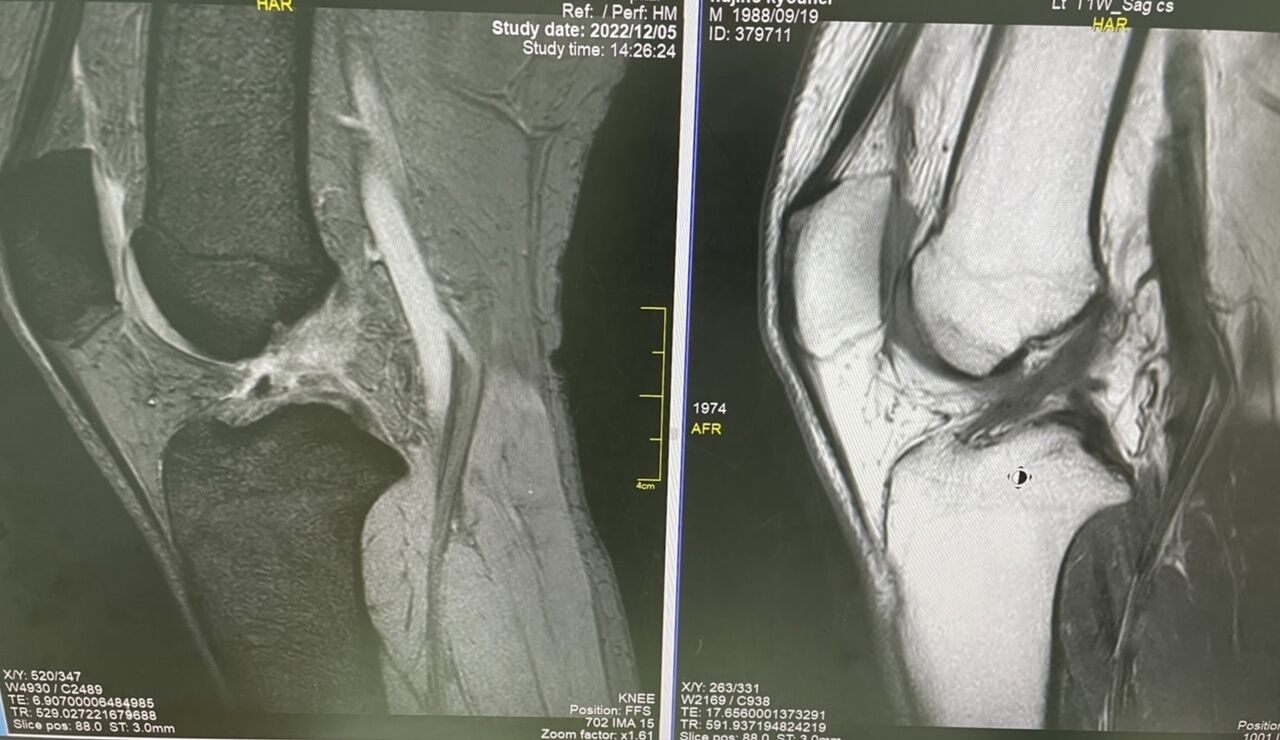

自営業でもあり、仕事を休むことが出来ず

保存的加療を、希望されました

装具療法を開始し、筋肉トレーニング、

膝、足部のアライメントを重視して、

リハビリを開始しました。

3ヶ月で、靭帯の癒合を、確認でき、

軽くフットサルができるようになりました

こういう状態は、なかなかありませんね

3ヶ月経過